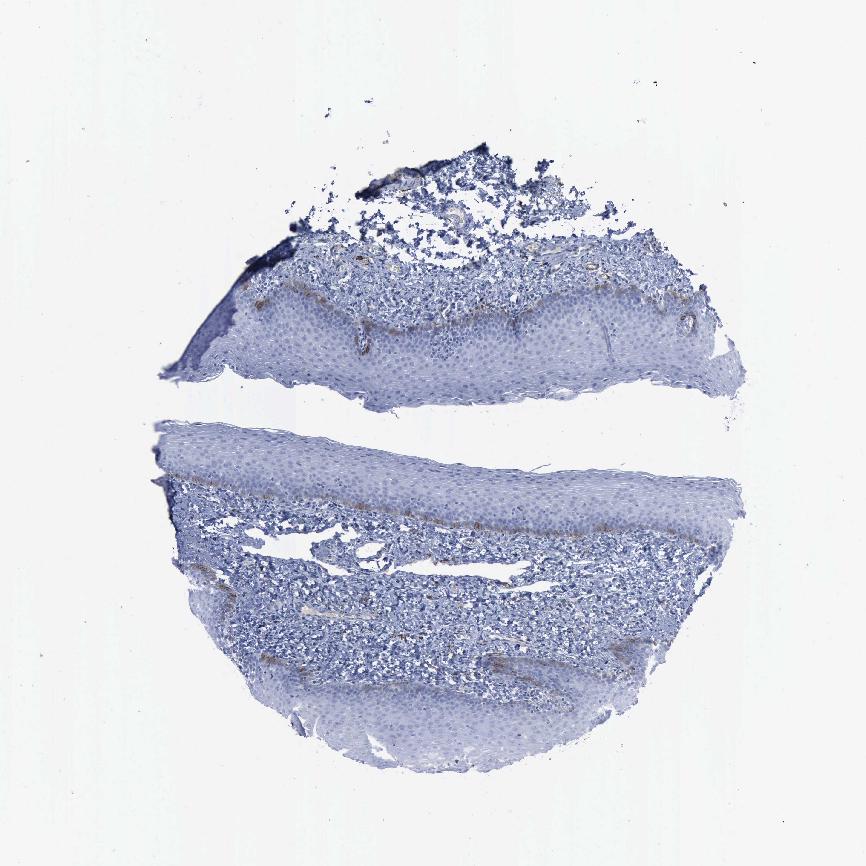

TISSUE PRIMARY DATA ORAL MUCOSA Show tissue menu

Oral mucosa

ORAL MUCOSA - Antibody stainingi

Antibody staining in the annotated cell types in the current human tissue is reported as not detected, low, medium, or high, based on conventional immunohistochemistry profiling in selected tissues. This score is based on the combination of the staining intensity and fraction of stained cells.

Each image is clickable and will lead to virtual microscopy that enables deeper exploration of all samples and also displays staining intensity scores, fraction scores and subcellular localization as well as patient and tissue information for each sample.

Antibody HPA004765Antibody CAB000143Antibody CAB001995

Squamous epithelial cells MediumMediumLow